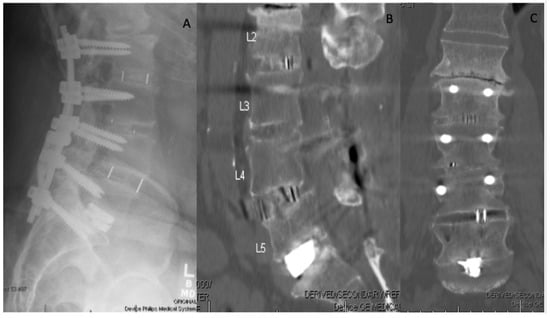

- Mokawem, M.; Katzouraki, G.; Harman, C.L.; Lee, R. Lumbar interbody fusion rates with 3D-printed lamellar titanium cages using a silicate-substituted calcium phosphate bone graft. J. Clin. Neurosci. 2019, 68, 134–139. [Google Scholar] [CrossRef] [Green Version]

- Mobbs, R.J.; Coughlan, M.; Thompson, R.; Sutterlin, C.E.; Phan, K. The utility of 3D printing for surgical planning and patient-specific implant design for complex spinal pathologies: Case report. J. Neurosurg. Spine 2017, 26, 513–518. [Google Scholar] [CrossRef] [PubMed] [Green Version]

- Mobbs, R.J.; Parr, W.C.H.; Choy, W.J.; McEvoy, A.; Walsh, W.R.; Phan, K. Anterior Lumbar Interbody Fusion Using a Personalized Approach: Is Custom the Future of Implants for Anterior Lumbar Interbody Fusion Surgery? World Neurosurg. 2019, 124, 452–458.e1. [Google Scholar] [CrossRef] [PubMed]